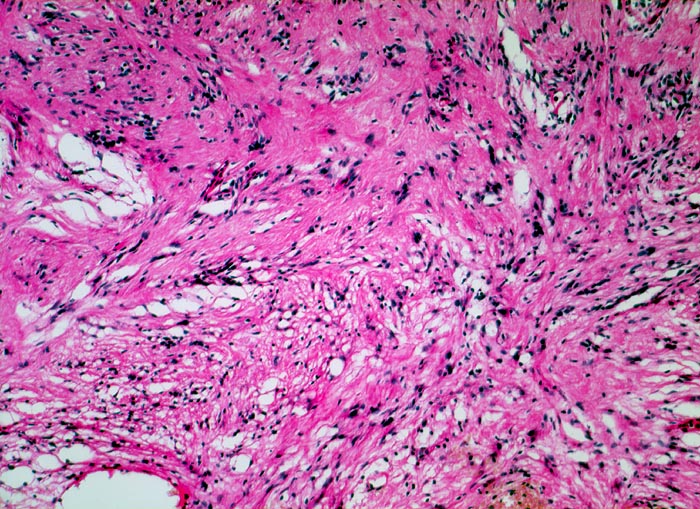

Die histomorphologischen Befunde sind sehr variabel. Am häufigsten bestehen die Tumoren aus Zellzügen mit bipolar orientierten länglichen oder gewellten Kernen und langen Zellfortsätzen. In den sogenannten Antoni A Arealen (> 4295) sind die Zellen in kompakten Bündeln angeordnet, teilweise in Form von Verocay bodies (> 493) (alternierende Anordnung von Kernreihen und Zellfortsätzen). In den Antoni B (> 4296) Arealen bilden die Fortsätze der eher sternförmigen Tumorzellen ein lockeres Geflecht. Einzelne grosse, unregelmässig geformte und hyperchromatische Kerne und flächenhafte Nekrosen, Hyalinisierung oder fokale Verkalkungen sind Ausdruck degenerativer Veränderungen (sogenanntes ancient schwannoma (> 4299)) und dürfen nicht als Zeichen der Malignität fehlinterpretiert werden.

• Biphasischer Tumor mit überwiegend kompakten (Antoni A Muster) und kleinen lockeren, hellen Arealen (Antoni B Muster).

• Antoni B Muster: Lockerer Tumorzellverband mit runden Kernen und spinnwebenartigen Zellfortsätzen.